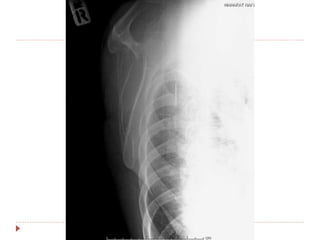

 Film right shoulder AP , transcapular

 Film right humerous AP , lateral

Right anterior shoulder dislocation

with avulsion fracture right greater

tuberosity

 Flim right shoulder AP , transcapular หลัง CR

investigation  Film rightshoulder AP , transcapular  Film right humerous AP , lateral

Imp : Right anteriorshoulder dislocation with avulsion fracture right greater tuberosity

Treatment  Closed reduction Pain control : pethidine 1 amp iv stat  Sedation : valium 1 amp iv stat  Traction-countertraction  Interlocking arm sling  Flim right shoulder AP , transcapular หลัง CR  F/U 2 week